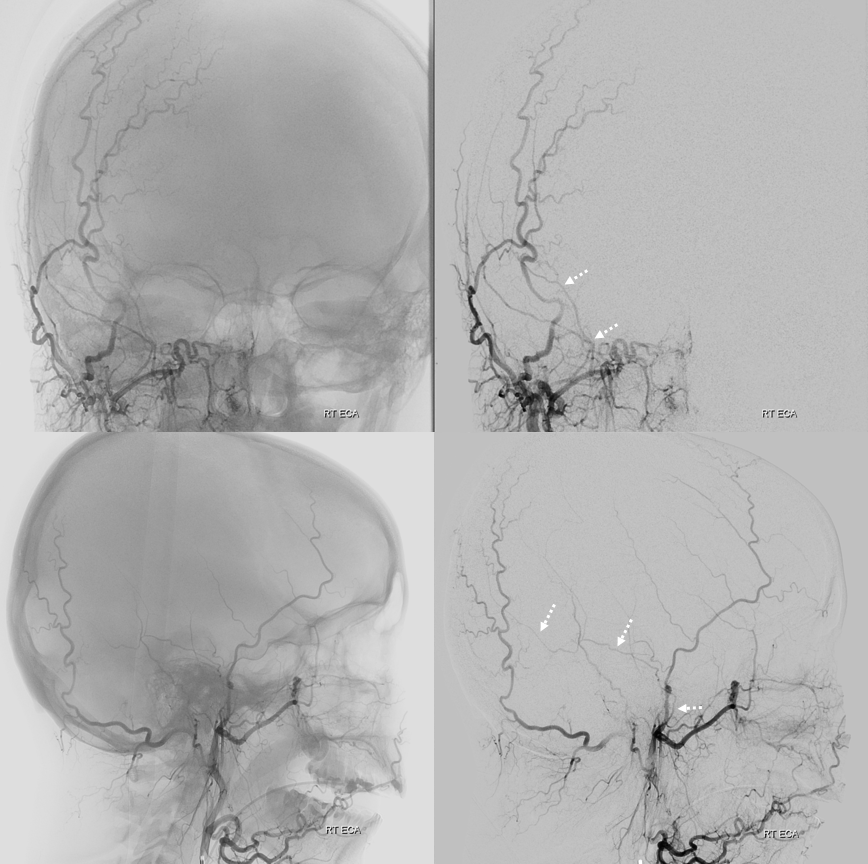

ECA with missing frontal division of MMA — petrosquamosal branch is shown by dashed arrows